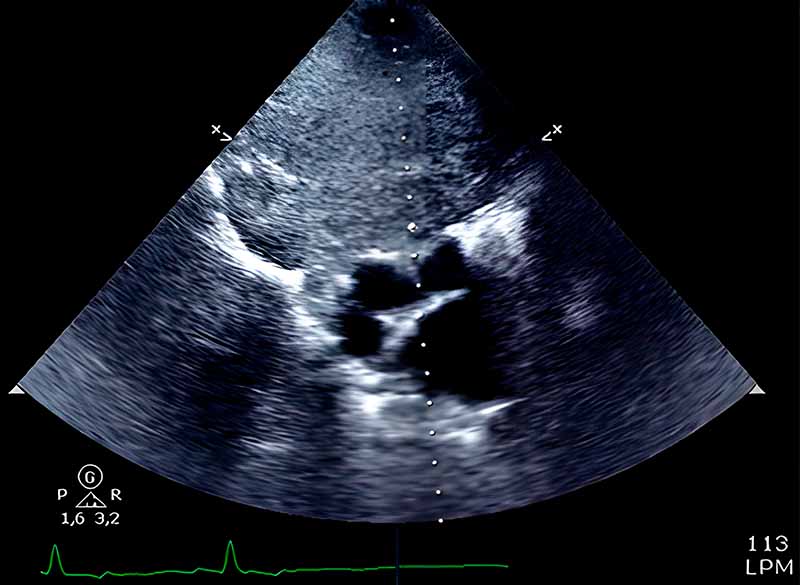

Estudio Ecográfico Especializado (DXIA): Realizado en vigilia (sin protocolo de sedación). Se confirmó la presencia de una masa heterogénea de gran volumen (>15-20 cm), con componentes cavitarios focales. La lesión ejerce un efecto masa compresivo significativo sobre la base cardíaca.